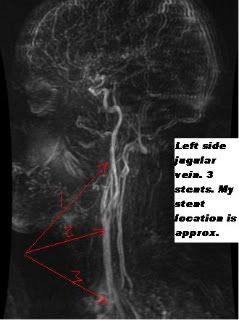

Please meet Mark Miller. Here is an image he has graciously supplied for this interview showing the stents in his jugular vein.